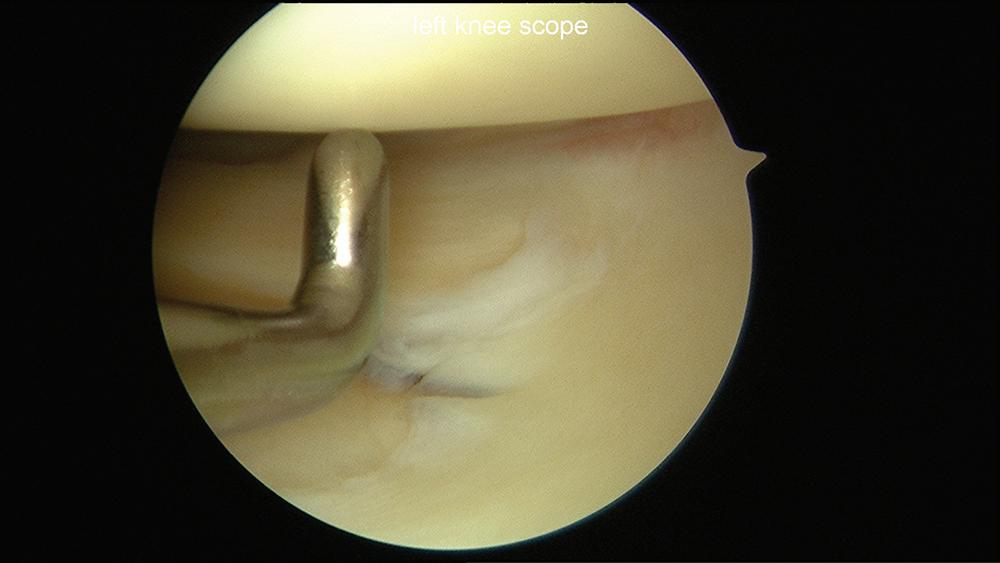

■ Thus, the correct visual orientation of the lateral compartment is maintained. The entire lateral meniscus should be probed and inspected, especially the posterior horn where tears are often missed (Figs. 1-10 and 1-11).

Figure 1-10 Arthroscopic photograph of the left knee shows assessment of the lateral compartment.

Figure 1-11 Arthroscopic photograph of the left knee shows assessment of the lateral meniscus.